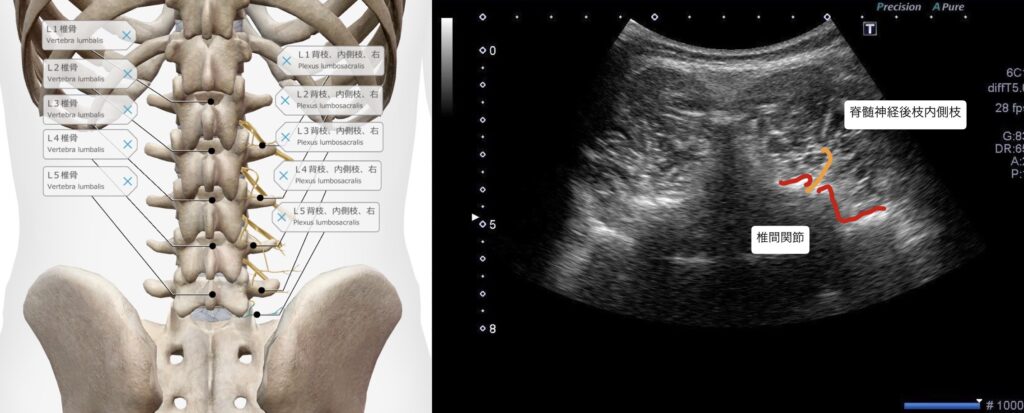

・超音波エコーの観察で、腰椎L4/5番の椎間関節にファシア癒着部位を確認。

・腰椎椎間関節L4/5の脊髄神経後枝内側枝に鍼通電を行った。

・痛みは脊髄神経後枝内側枝周囲の環境悪化、ファシア癒着による痛みの可能性が高い。